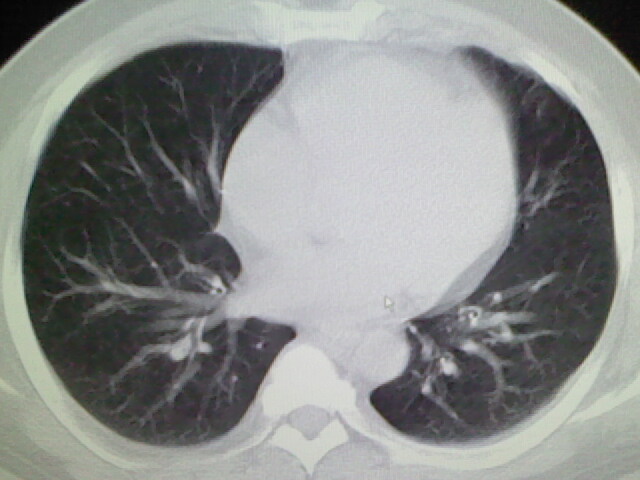

标题: CT17932:临床怀疑肺栓塞

男,34岁,自觉右侧胸痹,胸闷3天余

左肺上叶舌段少许炎症。

肺纹理分布较均匀,暂不提示肺梗塞